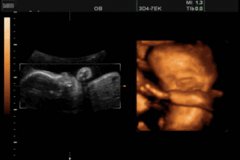

怀孕六个月男胎儿图

怀孕六个月也就是孕期21周-怀孕24周,此时的胎儿体重开始大幅度的增加,看上去已经很象小宝宝的样子了,不过皮肤依然是皱的,红红的,样子像个小老头。

怀孕六个月胎儿发育标准有大约以每周增加250克的速度在迅速增长。此时胎儿身长大约25~28cm,体重350克-800克。

从五官来看,21周时,小宝宝的眉毛和眼睑清晰可见。22周时,皮肤依然是皱的,红红的,样子像个小老头。牙齿在这时也开始发育了,主要是恒牙的牙胚在发育。

从四肢来看,胎宝宝在子宫羊水中游泳并会用脚踢子宫,羊水因此而发生震荡。手指和脚趾也开始长出指(趾)甲。

从器官来看,21周的他(她)已经能够听到声音了。肺中的血管形成,呼吸系统正在快速的建立。宝宝在这时候还会不断的吞咽,但是他(她)还不能排便。

我们通过怀孕6个月男胎儿b超图也可以看出,到了孕23周胎儿,23周的胎儿看起来已经很像一个微型宝宝了,他的身长大约20厘米,体重大约450克。由于皮下脂肪尚未产生,这时胎儿的皮肤是红红的,而且皱巴巴的,样子像个小老头。皮肤的折皱是给皮下脂肪的生长留有余地。